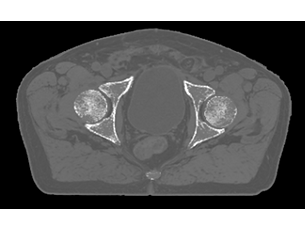

Whether for external beam radiation therapy (RT) or brachytherapy, integrating MR imaging into CT‑based planning can harness the power of MRI and transform patient management. With MRI’s excellent soft-tissue contrast, you can clearly see the tumor and organs at risk. So you can support accuracy in delineation and design the best possible treatment plans. Image courtesy of William Beaumont Health System, Detroit, USA - A superb MRI platform for radiation oncology

See clearly in treatment planning

Enjoy consistent, excellent image quality for multiple anatomies. Versatile arrangements of dStream coils work together with ExamCards tailored for RT to provide high-contrast images with high geometric fidelity. Quickly execute complete imaging protocols for prostate, female pelvis, brain, head and neck, and spine. - Learn and share MRI expertise

Whether for external beam radiation therapy (RT) or brachytherapy, integrating MR imaging into CT‑based planning can harness the power of MRI and transform patient management. With MRI’s excellent soft-tissue contrast, you can clearly see the tumor and organs at risk. So you can support accuracy in delineation and design the best possible treatment plans. Image courtesy of William Beaumont Health System, Detroit, USA - A superb MRI platform for radiation oncology

See clearly in treatment planning

Enjoy consistent, excellent image quality for multiple anatomies. Versatile arrangements of dStream coils work together with ExamCards tailored for RT to provide high-contrast images with high geometric fidelity. Quickly execute complete imaging protocols for prostate, female pelvis, brain, head and neck, and spine. - Learn and share MRI expertise